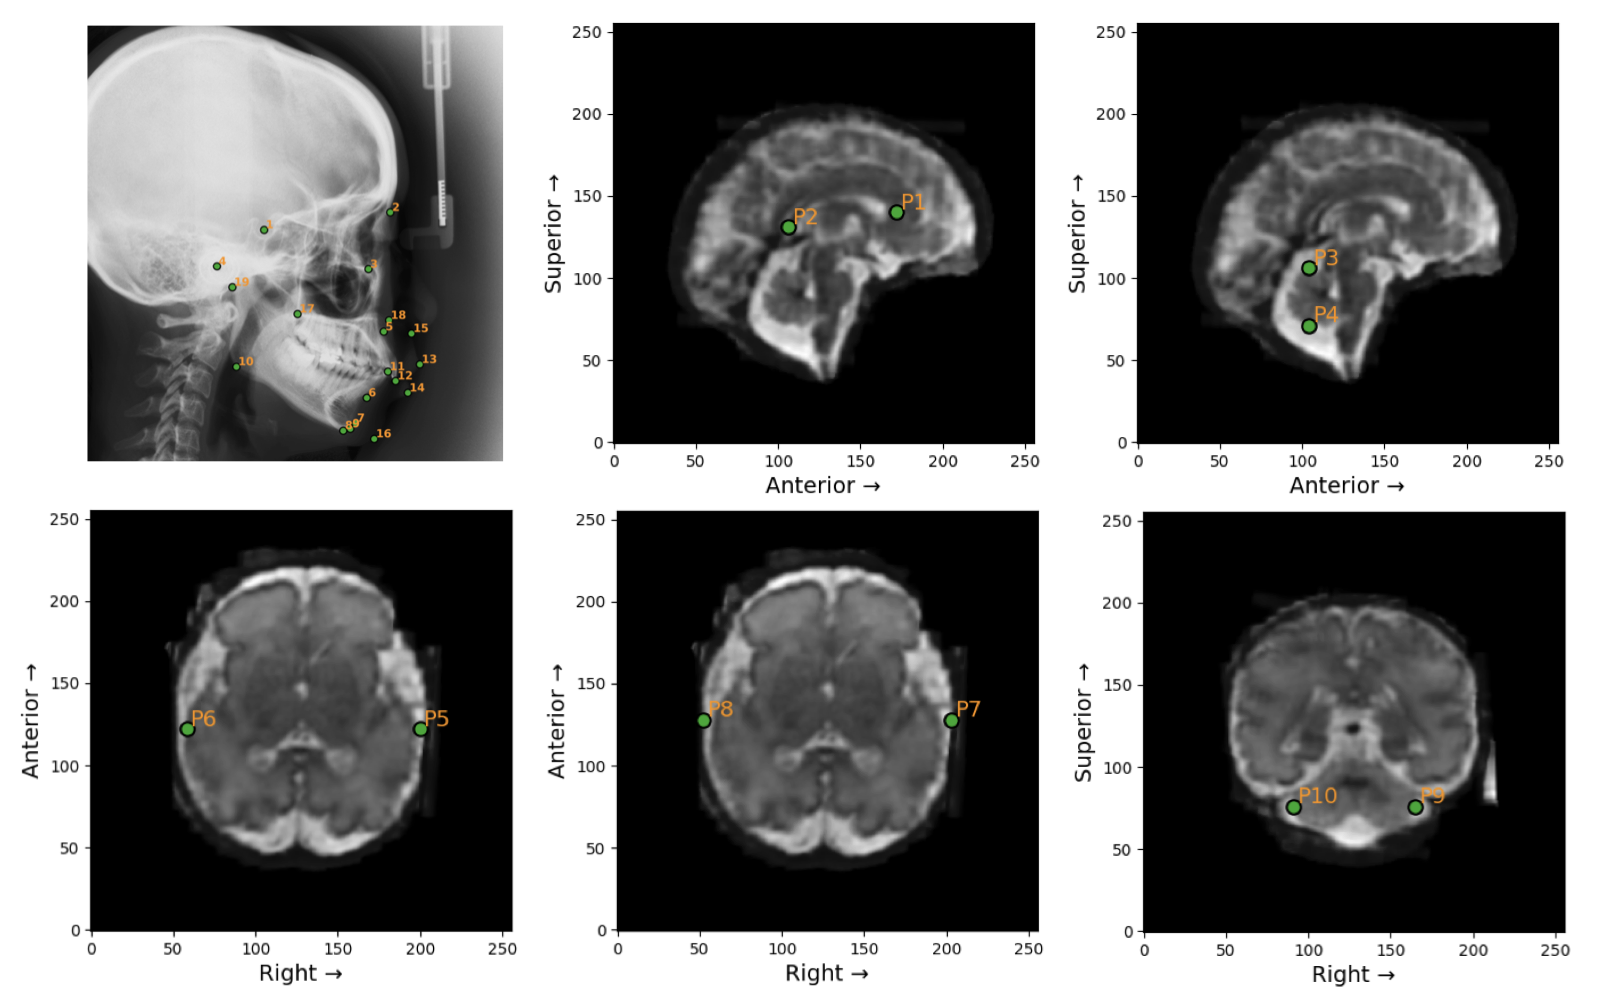

VLMs are prompted with task description and definition of angle or distance. Examples of landmarks in the Ceph-Bio-400 and FeTA24 datasets are shown below.

Figure 3: Landmarks in the Ceph-Bio-400 (top-left) and FeTA24 datasets. Ground truth angle and distance measurements are calculated from these landmarks.